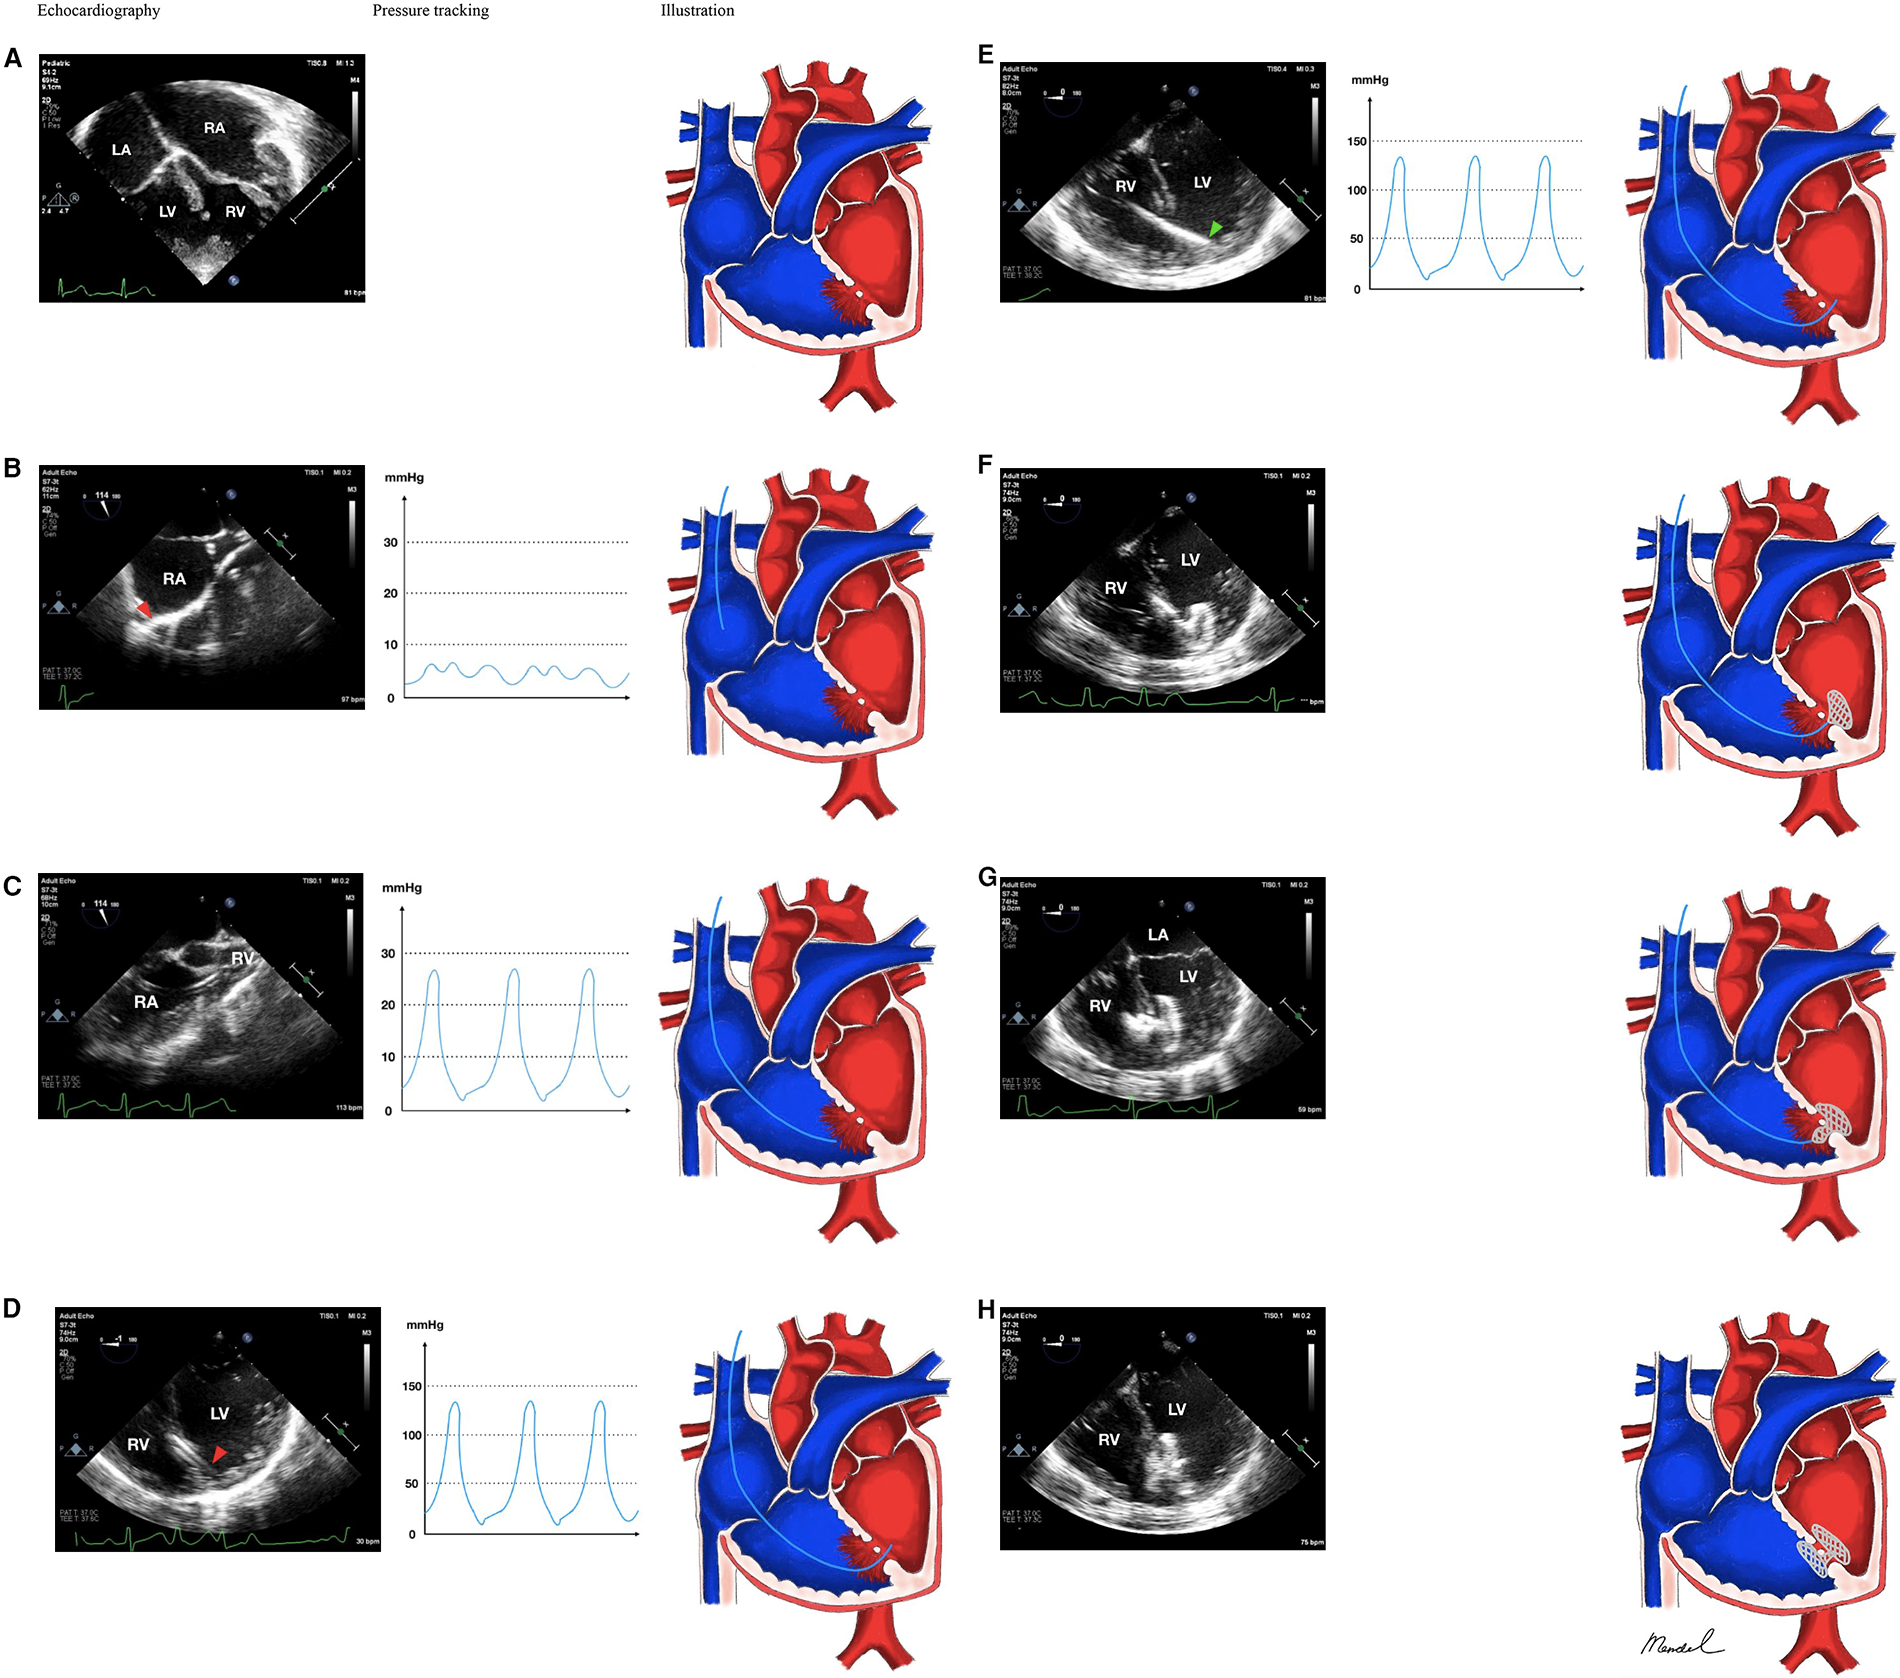

We chose to use the jugular vein approach to accomplish percutaneous transcatheter VSD closure. Preprocedural 98%; patient underwent general anesthesia. The patient was intubated using ETT No. 5.5% and 30% FiO2. 100% post-intubation saturation TEE revealed several muscular VSD with 2–3 mm and 12 mm diameters, 3 mm spacing between VSD, L to R shunt, AR (-), and TR mild with septal leaflet tricuspid prolapse. (Figure 1A). The decision was made to catheterize the right heart. The right femoral artery of the patient was punctured, and the patient then inserted a 4F sheath, heparin 1.000 IU, and MP sidehole 5F catheter. The right jugular vein was punctured; the MP sidehole was 5F and the sheath 6F was used. Following right cardiac catheterization (Qp:Qs 3.5, PVRi 5.23WUmsq, PVR 4.55 WU, PVR/SVR 0.16), we made the decision to correct the defect using an Amplatzer Septal Occluder (AGA) No. 16 mm using transjugular method. Through the muscular VSD, a 5F MP sidehole diagnostic catheter was introduced under the direction of transesophageal echocardiography (TEE). A 5F MP sidehole diagnostic catheter was introduced under the direction of transesophageal echocardiography (TEE) from SVC, RA, RV and LV through muscular VSD (Figures 1B–D). Using 0.035″ Amplatzer stiff wire, we change to 8F delivery sheath (Figure 1E). Full device deployment was successfully performed with several episodes of PVC storm and severe bradycardia (Figures 1F–H). Echocardiography evaluation showed no complications before, during, and after deployment of the occluder device (Figure 1H). Her symptoms and appetite steadily improved a week after the operation. She was able to engage in moderately intensive activities three months after the treatment without experiencing any discomfort.

Figure 1. Antegrade jugular vein approach in multiple-defect muscular VSD closure with pulmonary hypertension. (A) Multiple VSD. (B) 5F sidehole Multipurpose catheter was directed from SVC towards RA. (C) Catheter was then directed towards RV. (D) The catheter successfully crossed from RV into LV. (E) With the assistance of 0.035″ Amplatzer stiff wire, the catheter was changed with 8F delivery sheath. (F) The Amplatzer device occluder (AGA) No 16 mm was delivered and one of the disc was deployed in the LV side, (G) and RV side. (H) Device stowed in place; Red arrowhead showed the position of the catheter, green arrowhead showed the position of the delivery sheath. Notes: VSD, ventricular septal defect; SVC, superior vena cava; RV, right ventricle; LV, left ventricle; RA, right atrium; LA, left atrium.